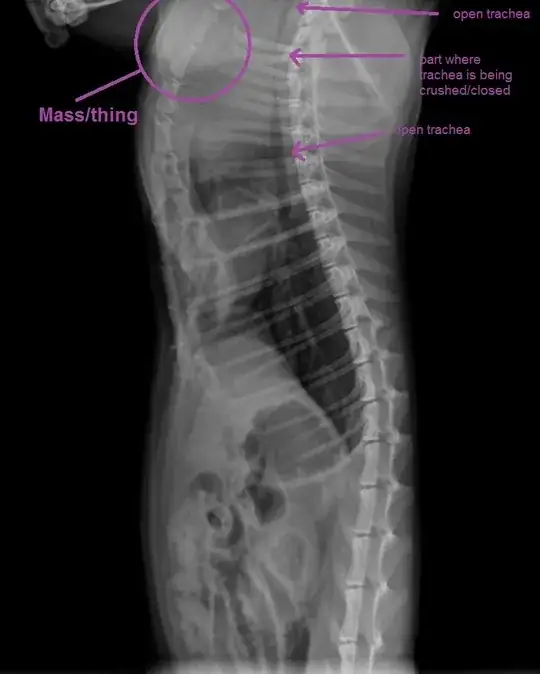

Our one year old, short hair, domestic calico started having what we thought was chest congestion / respiratory infection a few days ago: rattling sound in chest, wheezing, whistling breath when excited, swallowing difficulty, vomiting portions of meal during eating them (gag reflex triggered while eating). On about third day we took her to vet who did X-ray (attached) to find a mass of some sort in front of chest, pushing at and up on trachea causing it to almost close. the X-ray we looked over.

Vet does not think it is an infection as her colours are good, no running nose, and the mass seems very well-formed. Surgery is not a straight-off option as vet does not have scoping equipment so would be opening her up 'blind' and mass seems to be under the ribs and under some blood vessels. Vet is ready to do surgery if we insist, but does not think she will survive the act of being put under. Vet has commented that if this is a tumour it is very very strange for a cat so young.